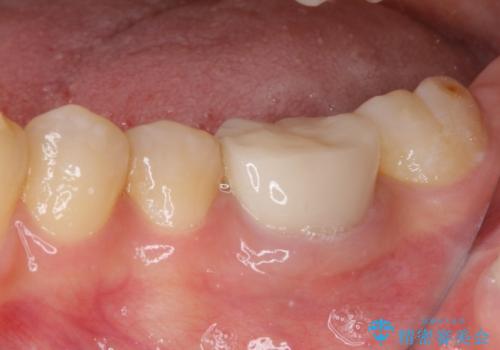

- 奥歯の形が気に入らないとのことで来院された患者様です。

形の変更を希望して、即日装着可能な歯科医院にて治療をしたそうですが、思い通りの形にできなかったとのことでした。

修正可能なように、従来通り技工所に発注して製作するオールセラミッククラウンにて補綴することとしました。